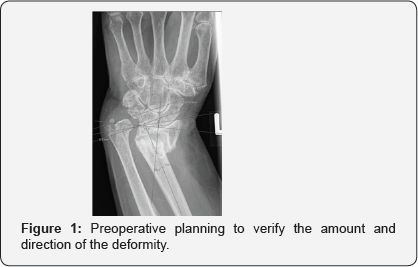

A volar approach to the distal radius extending proximally from the wrist crease along the flexor carpi radialis tendon using a 5-7cms incision, the radial artery identified and protected radially with pronator quadrates elevated along its radial and distal borders and the brachioradialis partially released from its insertion, the volar locking plate of the acumed set was used in all cases (standard size), where the distal end of the plate was aligned with the wrist joint, with the aid of k wires passing through the joint as well as under fluoroscopic image control to align the plate with the required volar tilt and radial inclination, once achieved the distal locking screws were applied. This was followed by the osteotmy being performed as close as possible to the level of deformity, and parallel to the wrist joint, once performed, the radius is pulled out to length with the aid of a laminar spreader applied at the osteotmy site and a cortical screw placed proximally to give the counter pressure required to regain the required radial height and ulna variance. Once corrected the plate was held in place and the first proximal screw was drilled through the oval hole to allow for further fine tuning followed by application of proximal locking screws through the rest of the plate holes (pictures), this was followed by cancellous bone graft harvesting from the same side iliac crest and the amount taken depending on the gap required to be filled at the osteotomy site, cortical bone graft was not added in any of the procedures, the pronator quadratus was brought back to its original position and the subcutaneous layer and skin were sutured using absorbable sutures. All patients had a below elbow well padded splint and discharged the same or the following day to surgery (Figures 1-4).